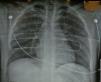

With these results, we decided to initiate the clinical phase. We performed the first lung transplantation with an out-of-hospital NHB donor using “bithermia preservation” in June 2010 in a 49-year-old patient with alpha-1 antitrypsin deficiency. We successfully carried out bilateral lung transplantation with excellent lung function after more than 12h of total ischemia. Since then, between June 2010 and July 2011, we have assessed 15 NHB donors. The chest radiography was normal in 6 donors (40%) (Fig. 2), 7 donors presented with pulmonary infiltrates, in one the radiography was of poor quality and in another it could not be done. Bronchoscopy was normal in 8 donors (53%), 3 presented abundant hematic secretions in the airway and in 2 there were findings of bronchial aspiration.